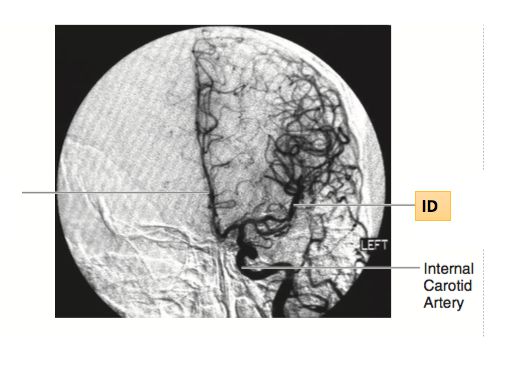

ID Vessel: _____